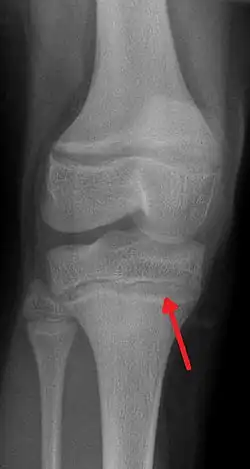

One of the clinical signs of rickets that doctors look for is cupping and fraying at the metaphyses when seen on X-ray.